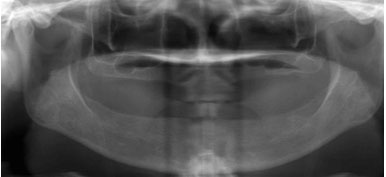

锥形束平板CT:

360°3D口腔透视